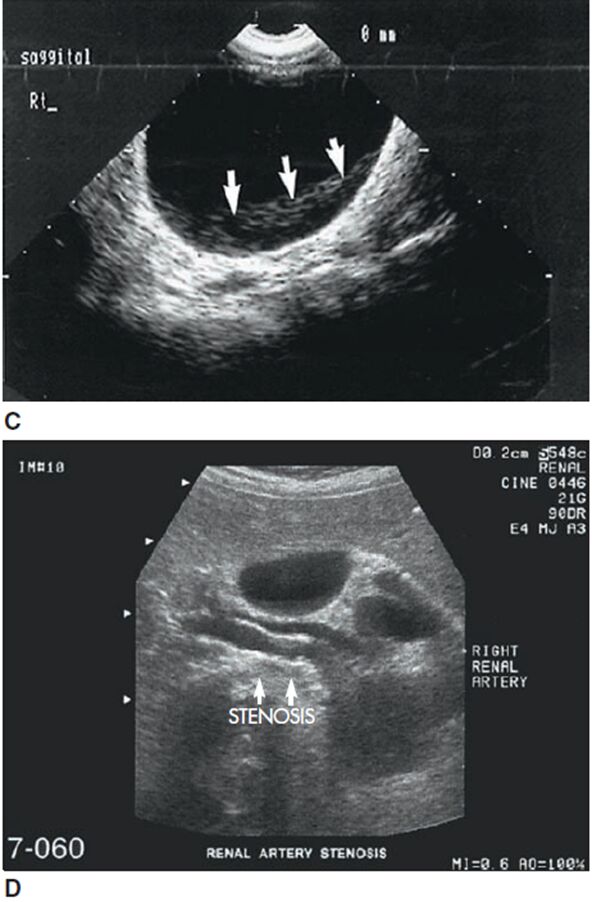

61.下圖之超音波影像中,編號51的區域最可能屬於下列何種假影?

截面厚度假影(section-thickness artifacts)又稱切片厚度假影(slice-thickness artifact)或部分體積假影(partial-volume artifact)。

1.產生原因:由於超音波脈衝在掃描平面中的長度和寬度有限,使得接收到的回波不只來自光束中心,還包含偏離中心(off-center)的回波,再加上除了軸向與橫向以外的第三維度之解析度—仰角解析度(elevational resolution;如下圖,與切片厚度有關)會因為要「塌陷」成二維圖像而無法呈現,導致產生假影。

2.圖片:截面厚度假影如下兩圖箭頭處,在本應無回聲的區域出現回聲。